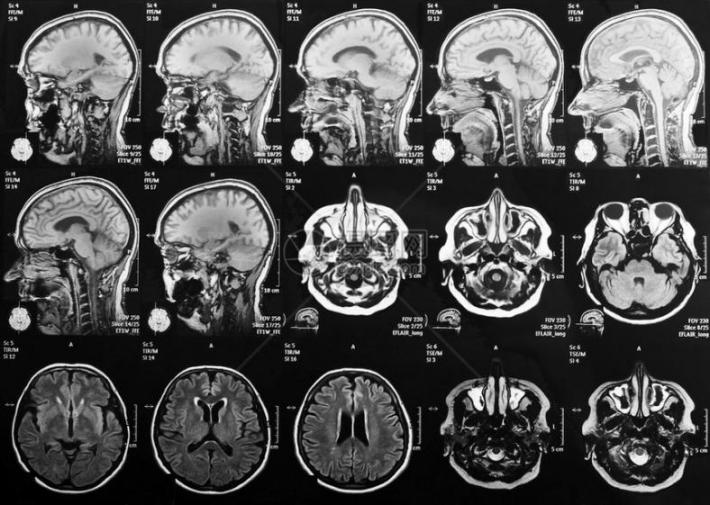

磁共振成像(MRI)就像是一种用强磁场给大脑照片的技术。人体内富含氢原子,这些氢原子在强磁场里会排好队,像小磁铁一样。这时,机器会发射出一种特殊的信号,短暂地“推”或“打扰”一下这些小磁针,让它们的队形暂时乱了。等这个“信号”停止后,被推乱的小磁针又会努力转回原来的方向。就在它们转回去的过程中,自己也会发出微弱的信号。机器捕捉到这些返回的信号,经过处理,就变成了我们看到的大脑清晰图像。

人脑在执行特定任务(如看图片、做数学题、回忆事情)时,与该任务相关的脑区可能会被激活。 科学家们借助fMRI可获得人体大脑在这些任务状态下的图像数据,通过对比不同任务下的大脑激活图,就能知道哪些脑区参与了特定类型的思考或感知。比如,观看人脸时,与面孔识别相关的‘梭状回面孔区’可能会被激活。

通过探测不同任务状态下大脑的血氧变化,磁共振技术得以标识忙碌的脑区。这为研究大脑工作机制,理解大脑的各种功能提供了强大工具。